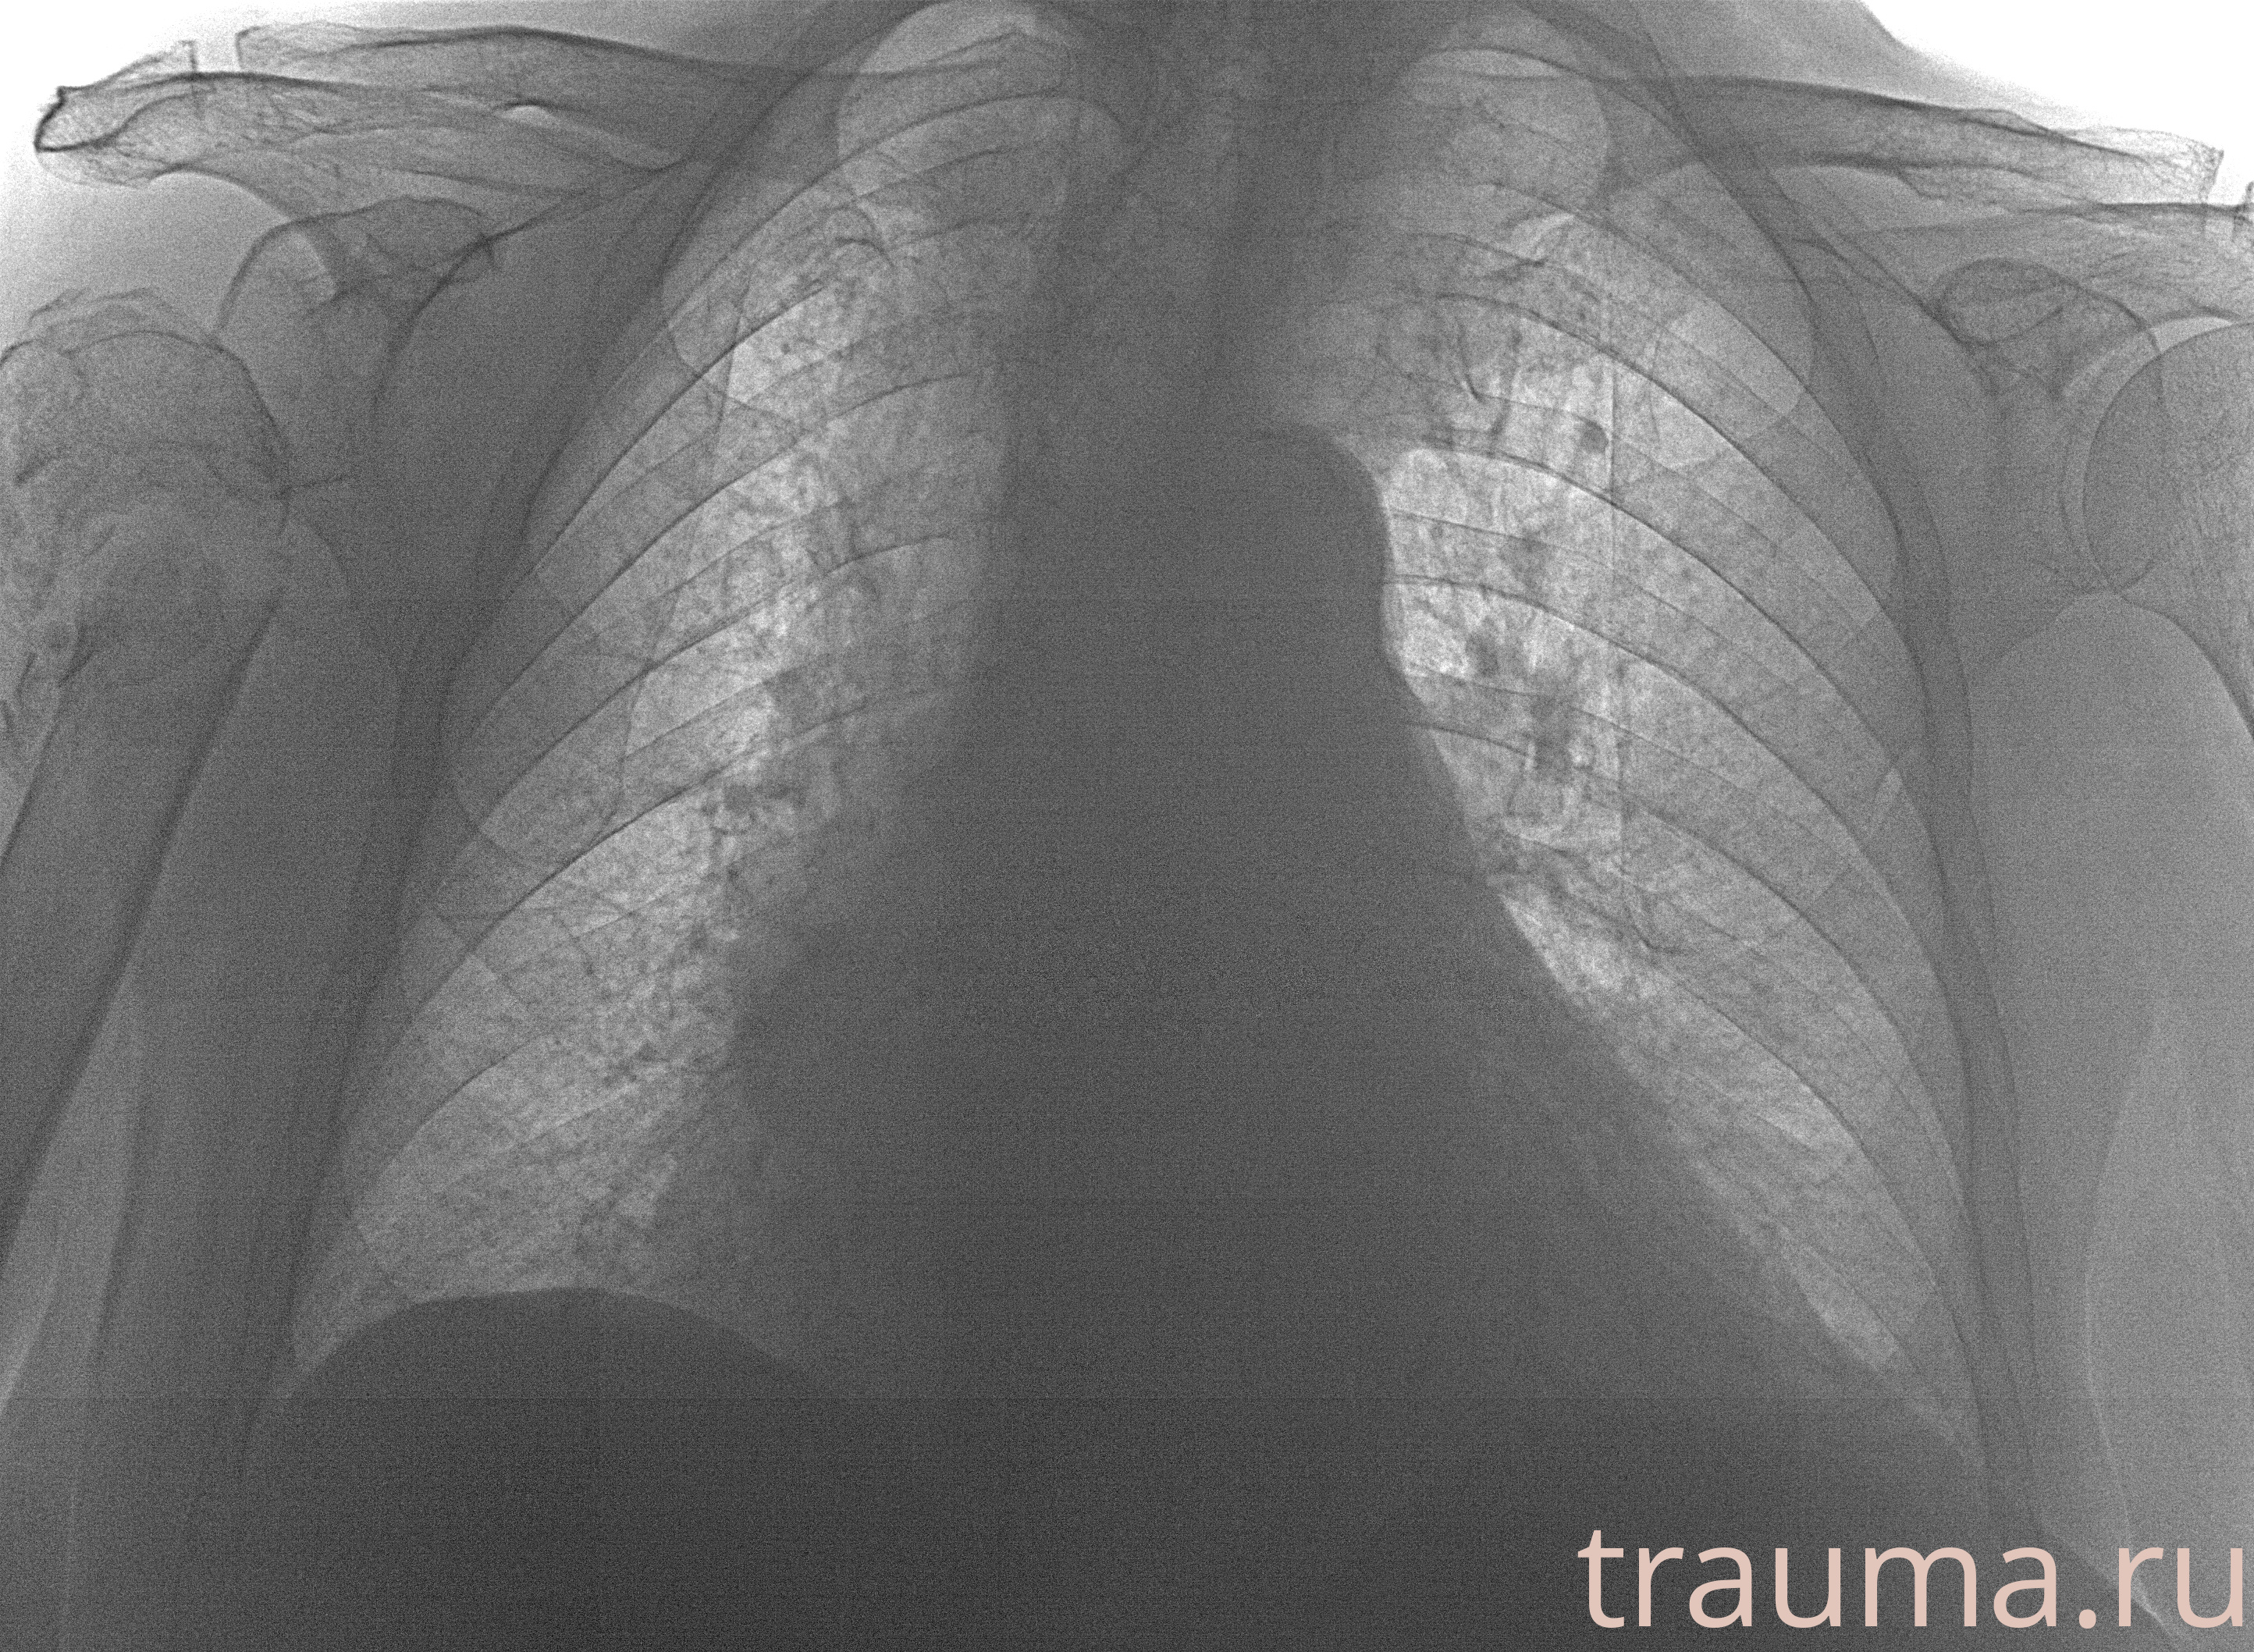

Рентгенограммы

Рентген на дому: по вашему адресу приезжает врач-рентгенолог, травматолог-ортопед с мобильным рентгеновским аппаратом, проводит диагностику травмы или заболевания, делает необходимые рентгенограммы, дает рекомендации по дальнейшему лечению. Получить качественные снимки в домашних условиях возможно благодаря уникальной методике, разработанной МосРентген Центром для института  Склифосовского